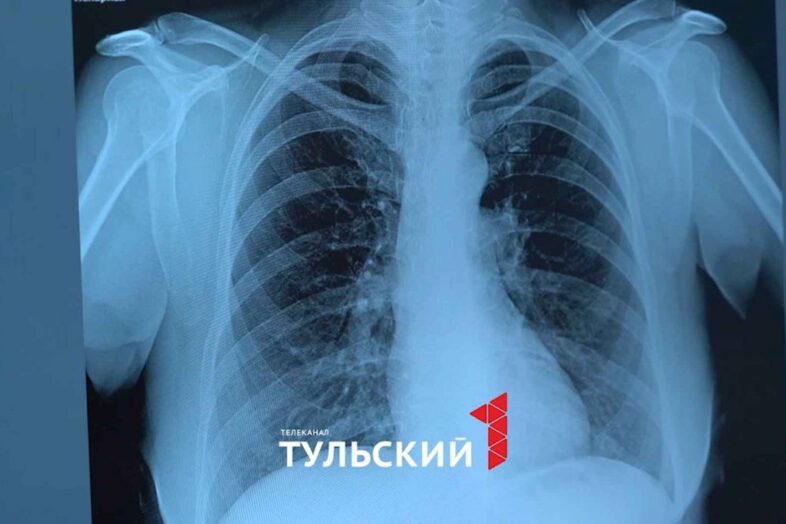

Фото: “Первый Тульский”

Такие снимки врачи получают по принципу обычной фотографии. Только вместо света, сквозь тело пропускают рентгеновские лучи. Мягкие ткани их легко пропускают, а кости – чуть хуже. Именно поэтому при переломах обязательно назначают рентген. Такую технологию уже 130 лет используют медики. Тулячка Елизавета Юрасова одна из них. Девушка окончила ординатуру, прошла практику и знания теперь подтверждает на деле. Серьёзное заболевание распознает по снимку всего за минуту.